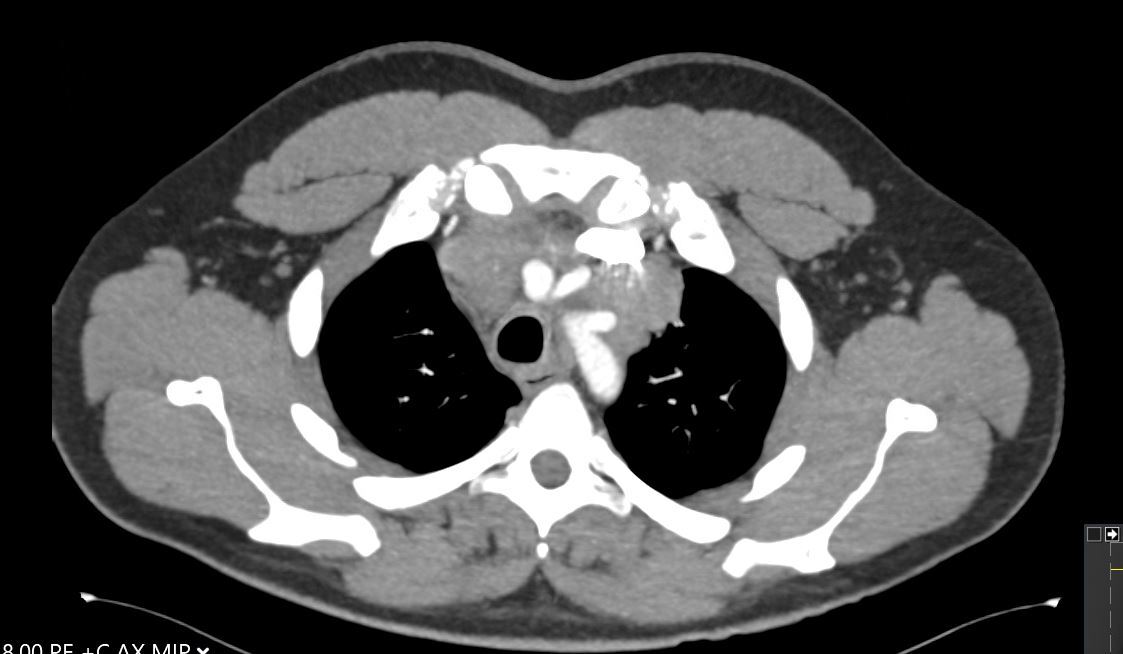

A 30-year-old man presents with dyspnea and is found to have an anterior mediastinal mass, as well as supraclavicular lymphadenopathy; biopsy of the mass is consistent with thymic carcinoma. Imaging shows his anterior mediastinal mass, lung and diaphragmatic lesions consistent with metastatic malignancy, and probable pericardial involvement with small pericardial effusion (Figures 1, 2, 3, and 4).

Fig. 1: CT image showing large mediastinal mass found to be thymic carcinoma. -

Fig. 2: CT image showing large mediastinal mass found to be thymic carcinoma. -